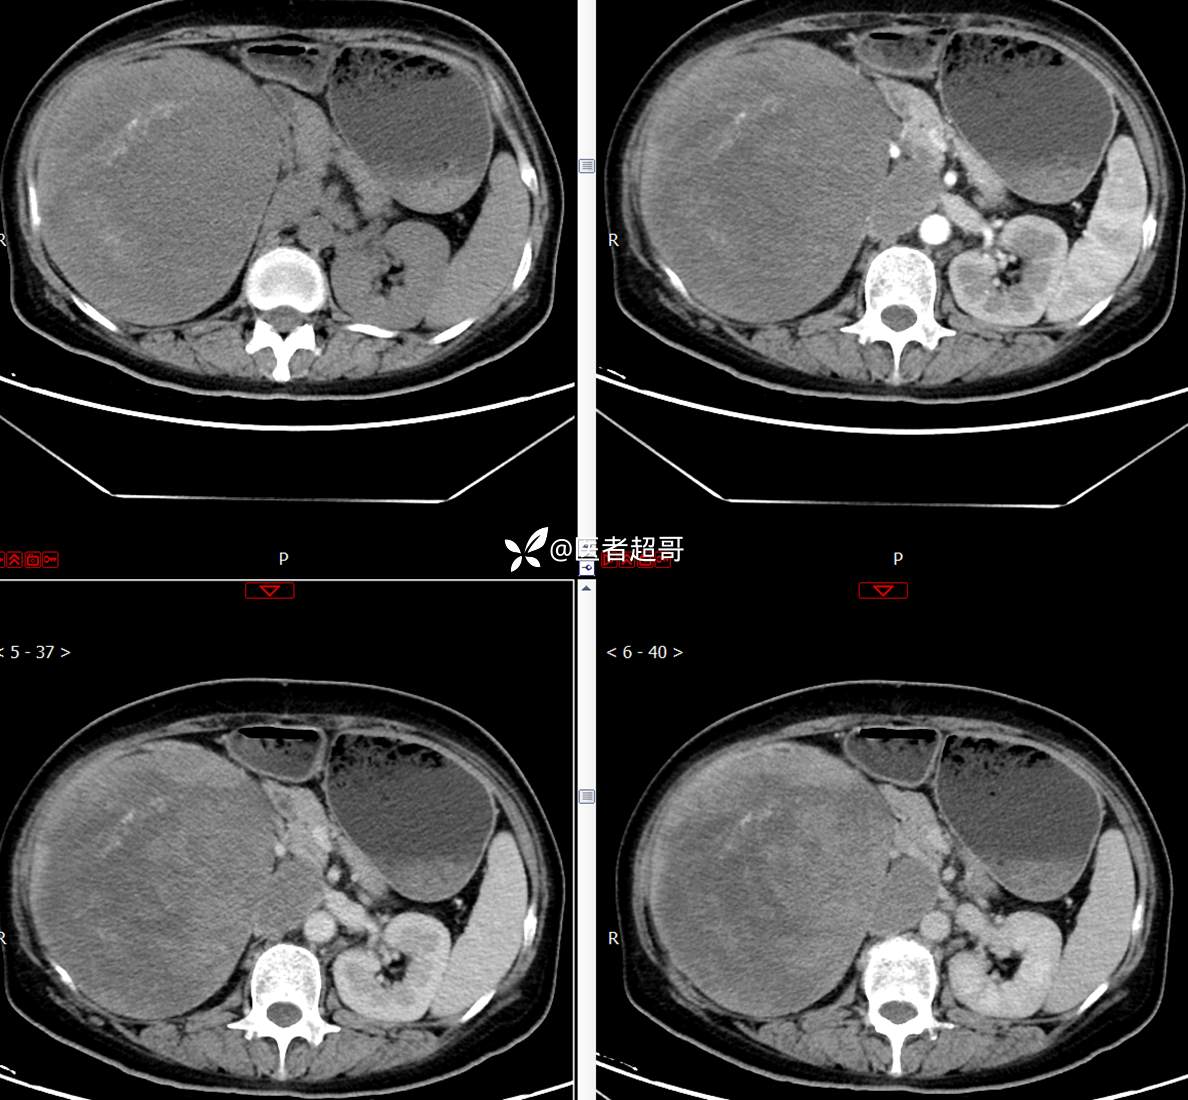

【影诊笔记743】腹腔肿物?腹膜后肿物?请先定位,后定性!有病理!

主 诉:发现右上腹肿物1周余。

现病史:患者1周余前发现右上腹有一半球形巨大肿物,约18cm*15cm大小,既往贫血病史3年余,诉乏力,易疲劳,偶有头晕,活动后心悸,无腹痛、腹胀,无恶心、呕吐,无尿频、尿急、尿痛,无排尿困难,患者为求进一步治疗,来我院消化内科就诊,门诊行肝.胆.胰.脾.肾彩超示:右肾上部囊实性占位,范围约18.0cm×11.7cm×16.4cm,边界清,形态规则,建议进一步检查,腹膜后实性结节。我科遂以“肾肿物”收治入院,患者自发病以来,神志清、精神可,睡眠、饮食可,二便正常,体重、体力略有下降。